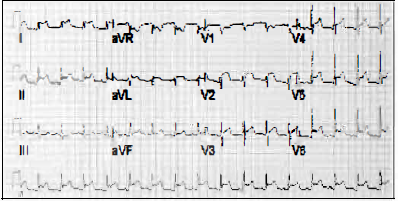

Paciente feminina, 15 anos de idade, apresentando quadro agudo respiratório há uma semana, deu entrada na emergência com dor precordial de forte intensidade que piorava em decúbito dorsal e inspiração profunda. Realizou o ECG abaixo.

O diagnóstico da paciente baseado nesse ECG é: